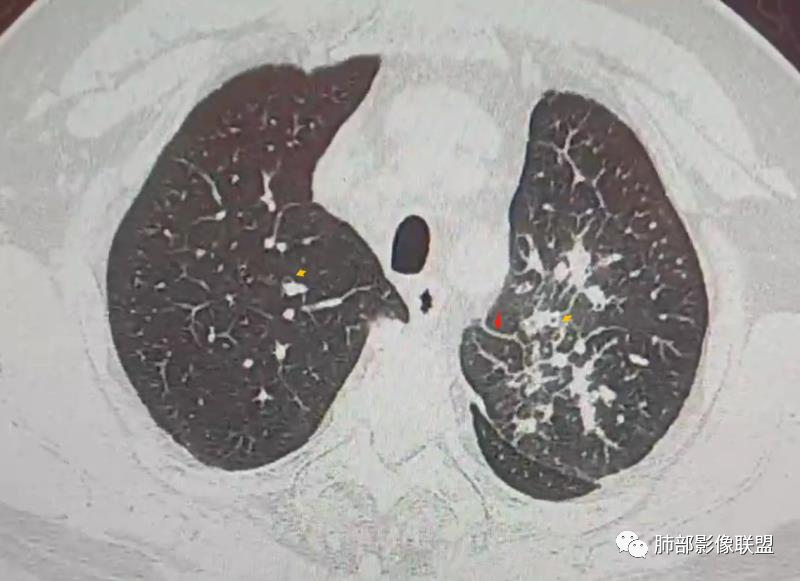

南边:这些是中轴间质增厚?树芽征?

Coke with ice:潘老师,这里是小叶间隔吧?串珠样的。

南边:是的。

南边:尖后段弥漫小叶间隔,中轴间质增厚,部分有结节感,大家考虑啥。

Coke with ice:我觉得是典型的癌淋,较大范围的,比如叶分布,甚至是整个单侧肺,单侧的肺小叶间隔增厚,极大概率是癌淋,另外一个疾病谱就是负压性肺水肿。

Coke with ice:这里有点像原发。隆突下也有大淋巴结。